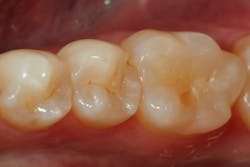

Case 1

A second premolar radiographically demonstrates decay, and the distal marginal ridge has been undermined and fractured (figure 1). A conservative preparation is made with a 330-carbide bur, and the caries is removed with a slow-speed round bur. A caries detection agent (Seek, Ultradent) is used to ensure that all decay is removed.